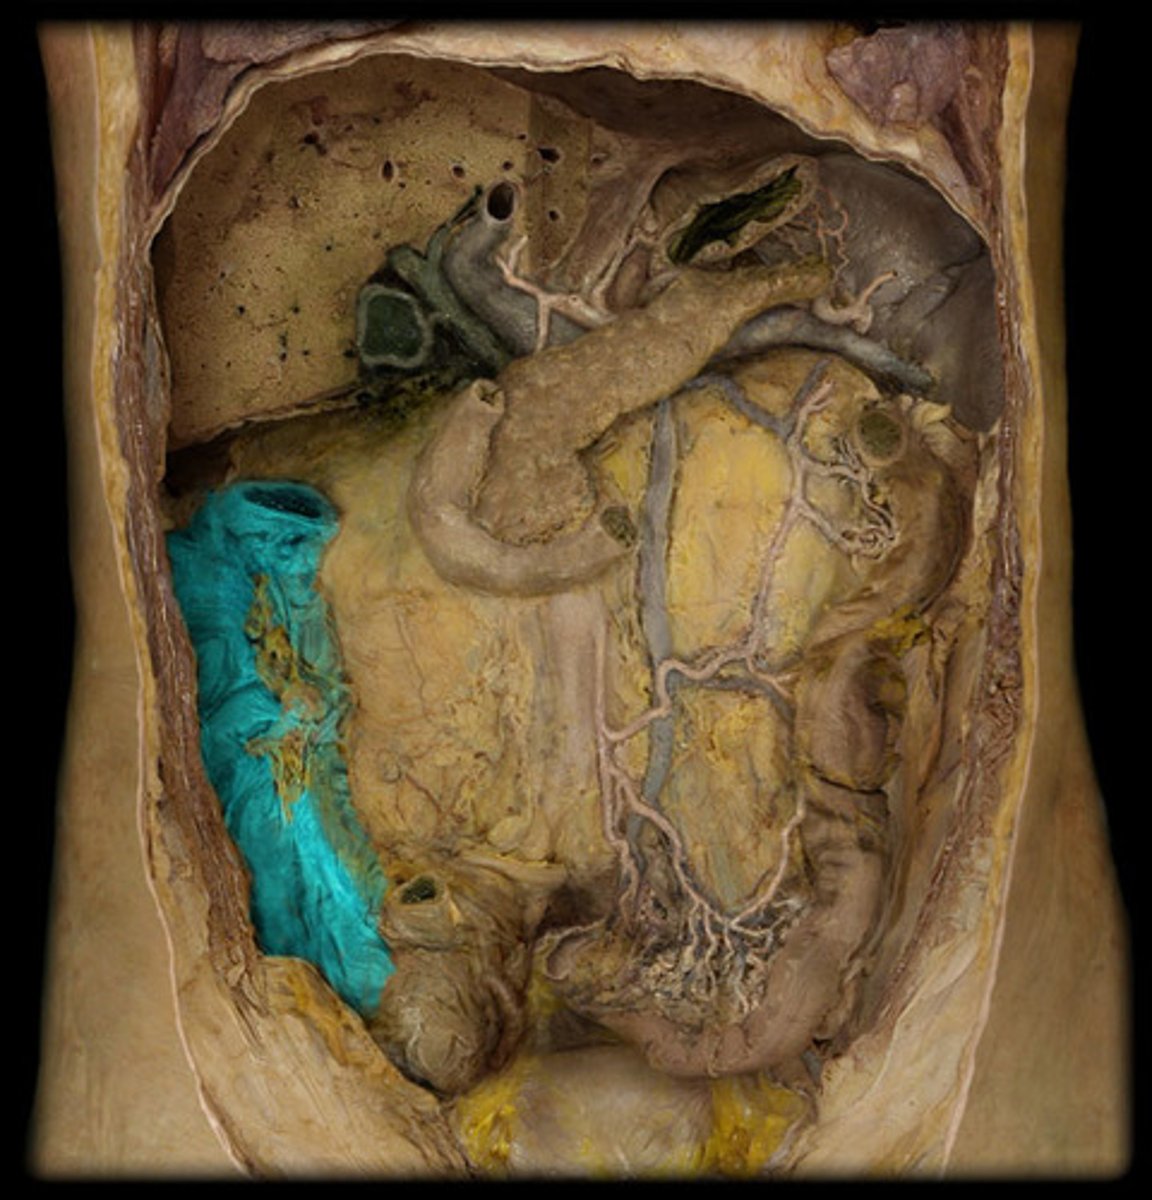

What is this?

Jejunum

Ileum

Ascending colon

Transverse colon

Descending colon

Sigmoid colon